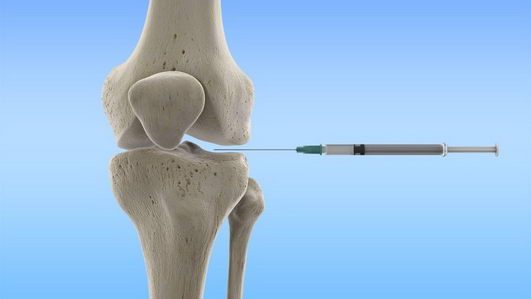

骨关节炎有时被称为退行性关节病,这是最常见类型的关节炎。在骨关节炎中,软骨被磨损。当软骨磨损时,骨头会相互摩擦。这会导致疼痛、肿胀、僵硬和移动困难。临床上医师会建议打玻尿酸治疗。但是,真的有效吗?

研究人员分析了24个先前对膝盖骨关节炎注射玻尿酸的大型试验发现,虽然有可测量到的益处,但它因太小而没有临床的意义。这意味着玻尿酸注射对大多数患者没有有意义的益处。

研究主持人da Costa 说,“我们的研究结果不支持广泛使用玻尿酸来治疗膝盖骨关节炎,”

但是,这个结论并不完全是新的,da Costa的小组只是比其他评论更大胆地表达了这一点。例如,美国骨科医师学会 (AAOS) 网站承认“最近的研究……没有发现玻尿酸能有效地显著减轻疼痛或改善功能。”

但 AAOS 总结并没有警告患者或临床医生远离注射。它说“一些”患者获得了疼痛缓解,而“一些”没有,并将注射描述为“尝试过所有其他非手术治疗方法”的患者的“一种选择”。

没有效益,却还有副作用

另外值得注意的是,数据确实显示注射玻尿酸并不是完全良性的。15 项试验 (6,462 名参与者) 详细报告了不良事件,da Costa 等计算出,注射的严重并发症风险显著增加 (相对风险 1.49,95% CI 1.12-1.98)。研究人员发现,接受玻尿酸的患者中有 3.7 % 经历了严重的不良事件,而接受安慰剂的患者中有 2.5 %。

来自 24 项大型对照研究 (包括 8,997 名膝关节参与者) 的系统性分析显示,相对于安慰剂注射,玻尿酸以 -0.08 分的标准化均数差 (SMD) 降低了患者的疼痛。但临床上重要程度的疼痛减轻需要 SMD 至少为 -0.37 点。这意味着玻尿酸注射 (又名粘性补充剂) 对大多数患者没有有意义的益处。

24 项试验中只有一项的 SMD 超过 0.37 点疼痛阈值,但它出现在 1983 年,对测量结果的偏差存在“高风险/一些担忧”,并且没有在英文期刊上发表。按他们进行的年份对试验结果的分析显示,它只是最早表明有实质性好处的。在 1983 年的那项研究出现之后,下一个大的研究出现在 1993 年;结合两者的数据,SMD 已经低于 -0.37 点。到 2004 年,共有 2,240 名参与者参与了 9 项试验,很明显这些注射没有明显的帮助。从那时起出现的试验只是加强了这一结论。